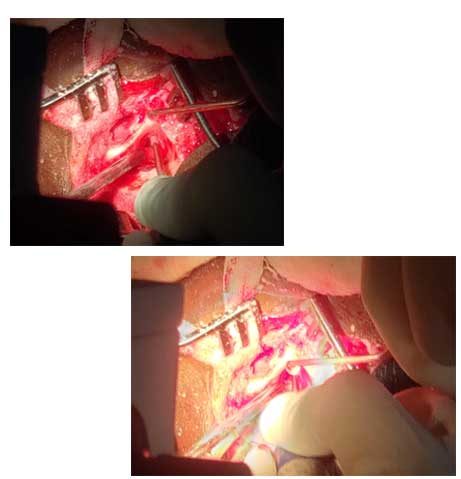

42/M Patient came with H/o self inflicted, cut throat Diagnosed -Self inflicted cut injury /zone-1 and 2 neck injury . Presented with severe bleeding, hypovolumic shock .Airway secured and fluids started . Pt was shifted to emergency OT and resuscitation started and stabilized by our anesthesia team. Patient underwent Emergency exploration of neck and bleeding IJV was ligated and ryles tube inserted .There were two penetrating wounds in neck , one in zone 1 which was exposed and Tracheostomy done. In zone 2, there was complete transection of thyroid cartilage and epiglottis, completely separated and tear went upto pyriform mucosa. Cartilage repair and mucosa repair done . It is first of its kind , cut throat injury with vessel bleed and pt revived in almost arrested stage and successfully surgical repair done .